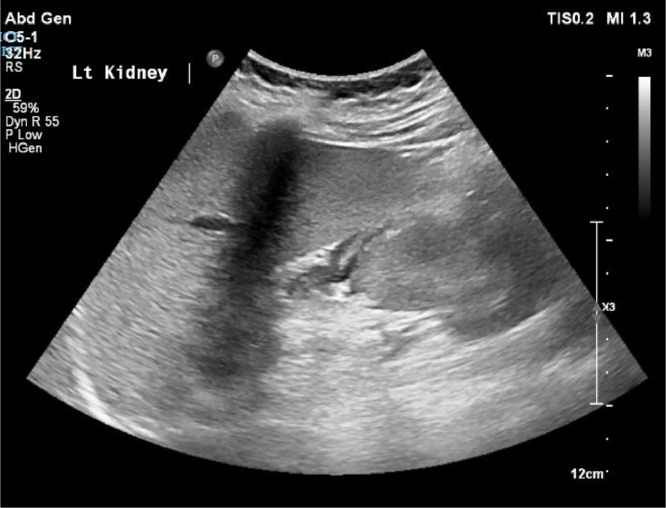

Adrenal haemorrhage in pregnancy is rare but can lead to significant maternal and fetal morbidity if unrecognised. We present the case of a 25-year-old woman in her second pregnancy, who was admitted at 34 + 4 weeks of gestation with severe abdominal pain. Despite initial unremarkable assessments, further imaging revealed a left adrenal haemorrhage, with evidence of prior right adrenal infarction, resulting in primary adrenal insufficiency. Haematological investigations later confirmed heterozygous factor V Leiden as a likely contributing factor. This report underscores the diagnostic challenges of adrenal pathology in pregnancy, where symptoms may overlap with more common conditions. Immediate management with hydrocortisone therapy, supported by a multidisciplinary team (MDT), was employed, with a successful outcome for both mother and child following delivery by caesarean section.

Abstract Image